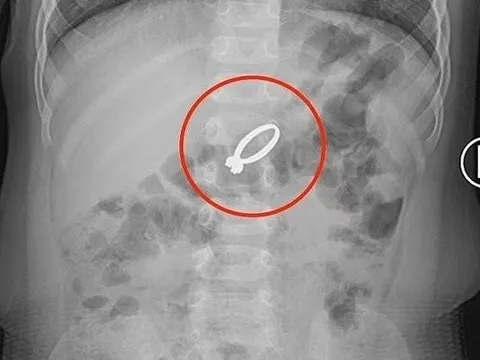

Bé trai vỡ khí quản, nguy kịch tính mạng do ngã vào kệ tivi

Ngày 4/4, bác sĩ tại Bệnh viện Nhi Trung ương cho biết, vừa tiếp nhận một bé trai 7 tuổi vào cấp cứu trong tình trạng nguy kịch.